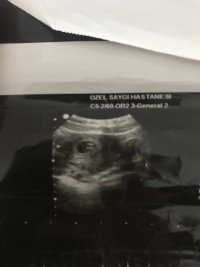

Merhaba .Bunlarda 6+4 günlük usg fotolarım.Ramzi teorisine göre de yorum yapabilir misiniz

Selamlar, bu yuvarlak kese olan bölümü yakın atar mısınız tam anlamı ile yorum yapamıyoruz görmediğimiz için